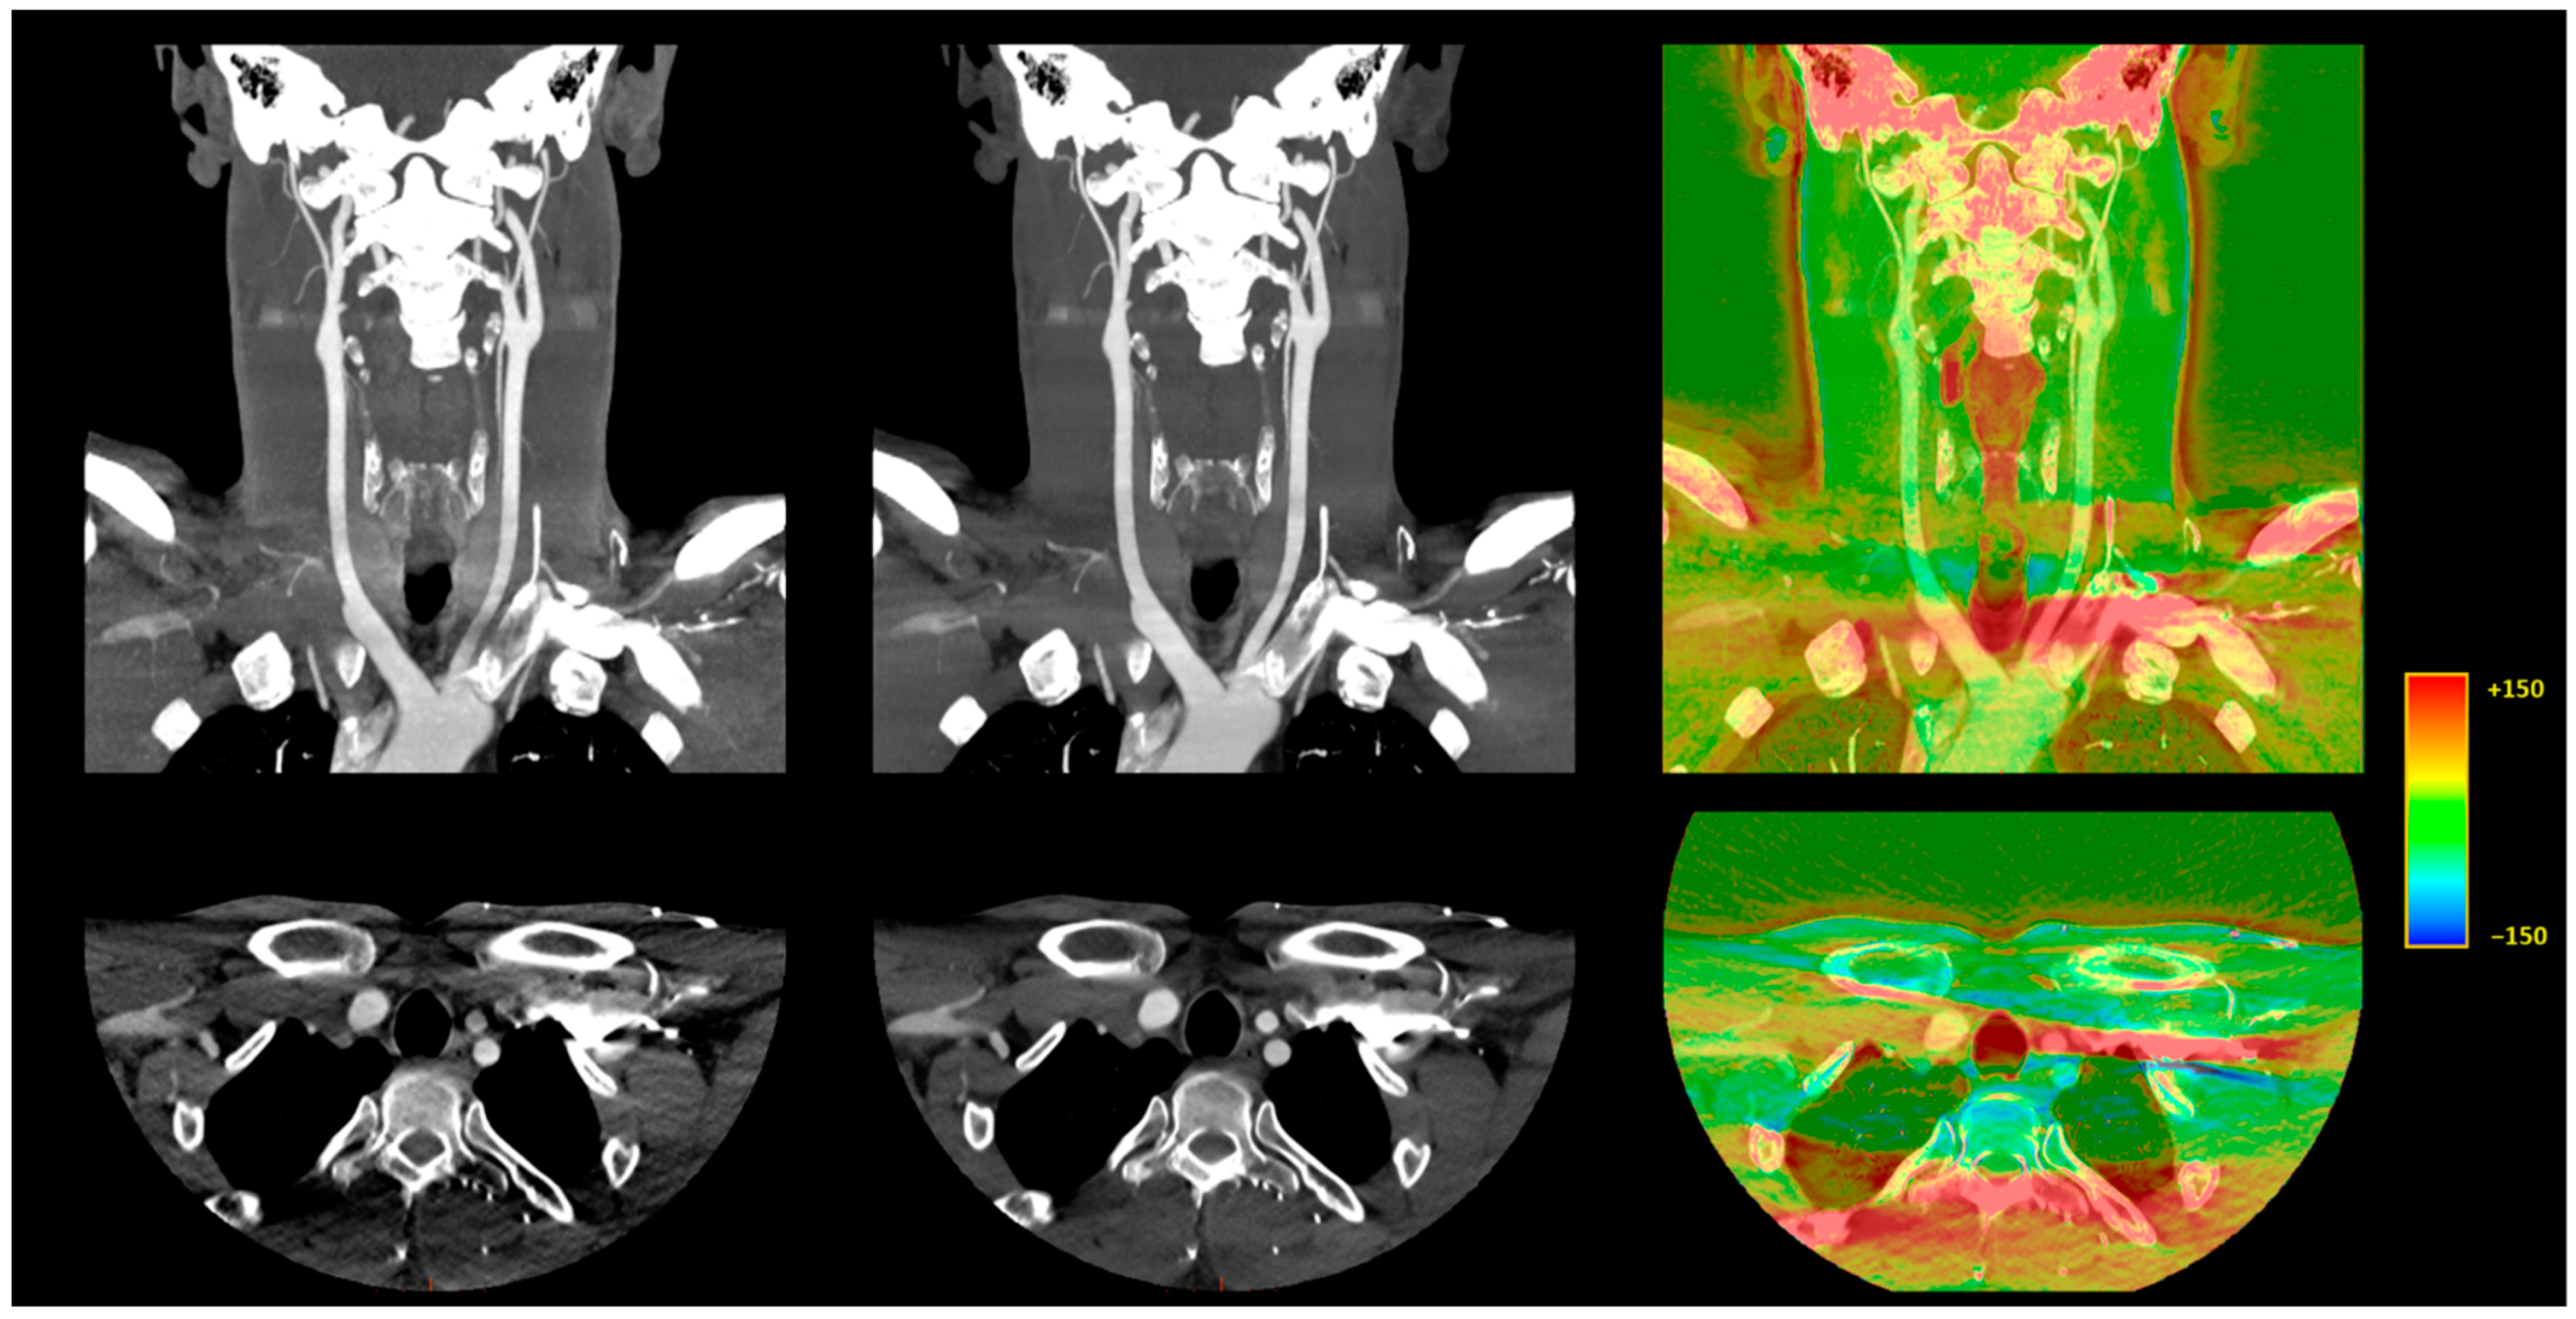

3.3.1. Image Signal Fluctuation with DLR vs. H-IR

3.3.2. Comparison of the Two Reconstruction Techniques at Constant kVp Value